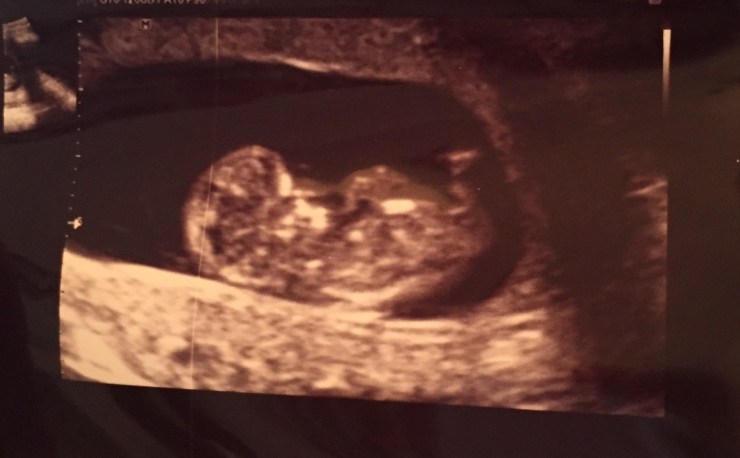

Yes, yessss. We hebben een (te) gekke quizvraag voor jullie. Na de geboorte van cutie Oscar van onze Anouk is er wéér blij babynieuws bij MOMspiration. Iemand van ons team verwacht namelijk een derde kindje! De termijnecho is achter de rug en de baby is door de voorlopige keuring heen. Een kloppend hartje, armpjes, beentjes, goede billen, 2 hersenhelften, een neusje, boven- en onderkaak en nog allerlei ieniemienie belangrijke onderdelen zaten erop en eraan.

Maar hé, van wie is die kleine baby van 5 centimeter?